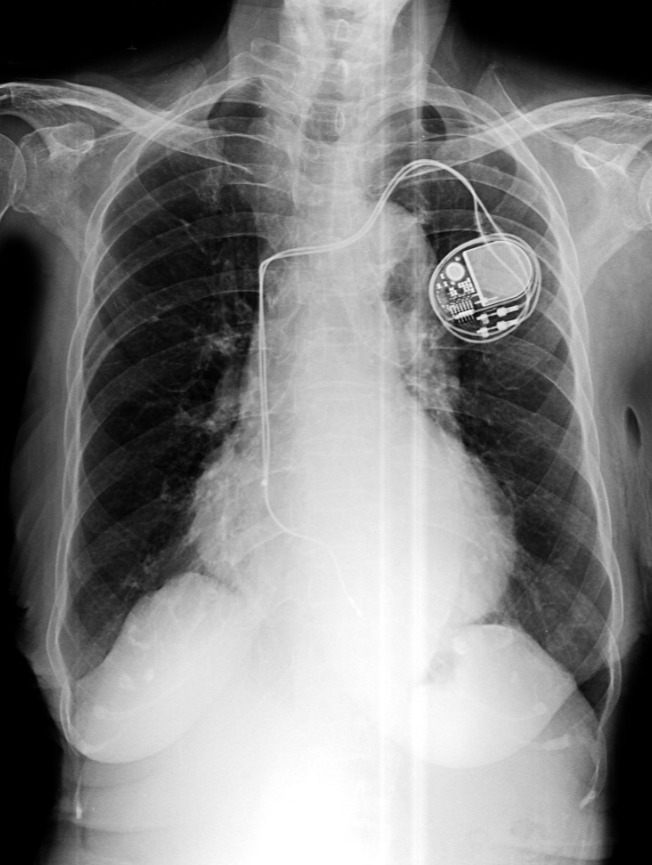

Pacemaker Surgeries Doctors in Pune for Reliable Heart Rhythm Management